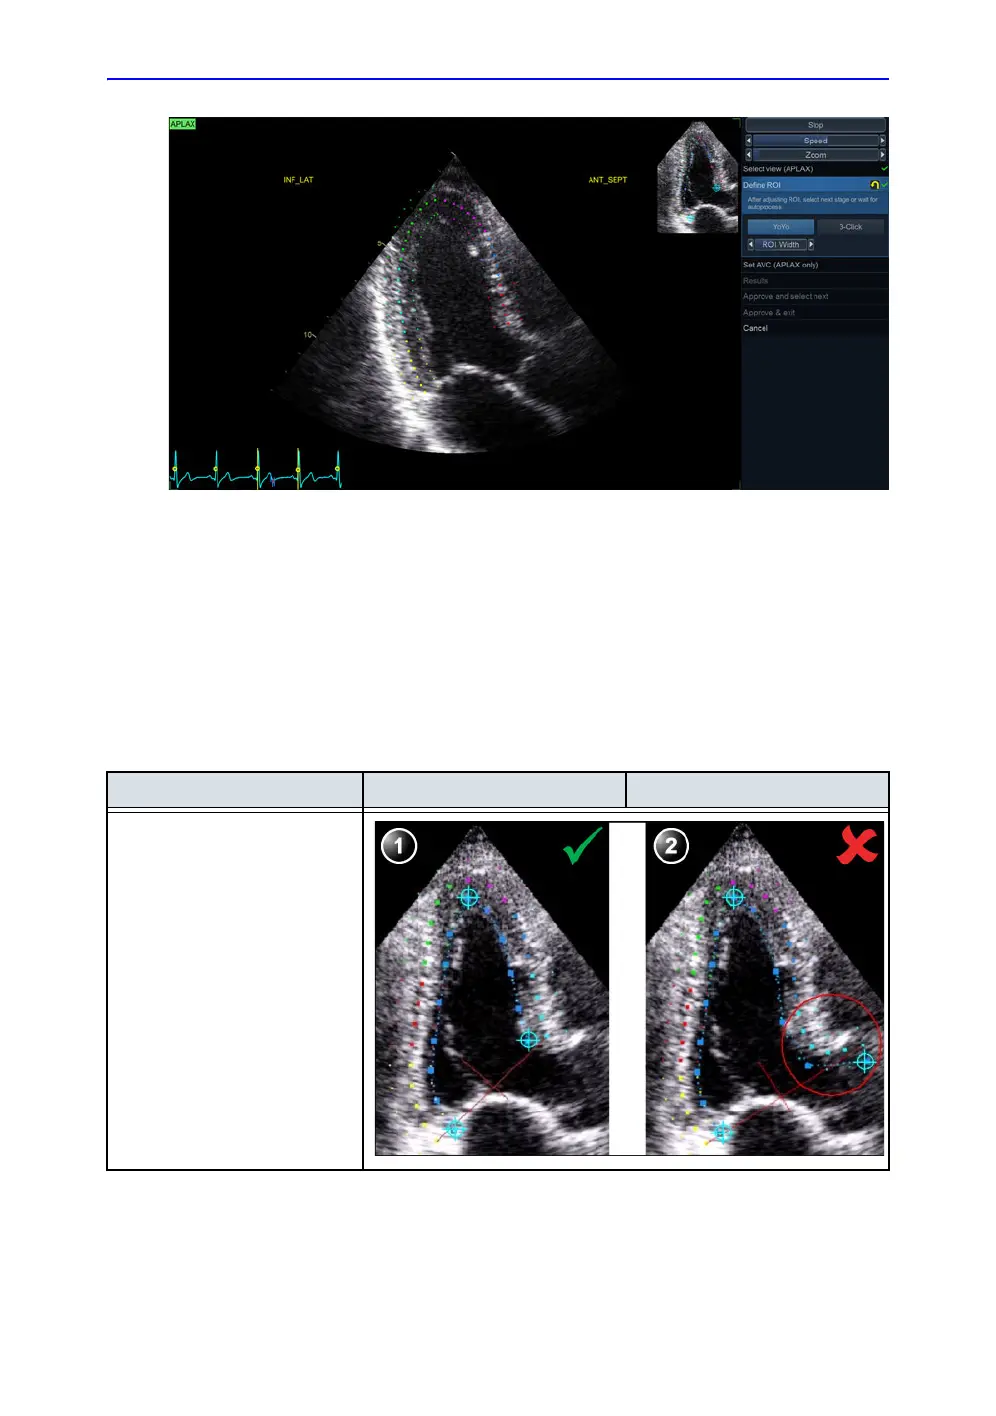

Figure 8-16. Defining a ROI

After placing the three points the ROI is displayed.

Guidelines when re-creating the ROI

Correct ROI definition is crucial to get good tracking. See use

cases below for common pitfalls.

Base Correct Wrong

1. Correct position of the base

points.

2. The ROI extends into the

aortic tract.